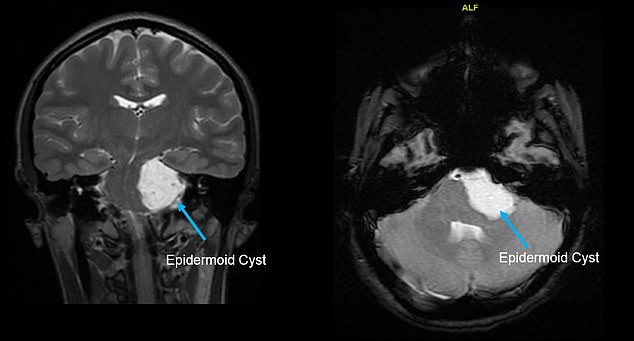

After one particularly bad sore throat, she went to the ER, where doctors performed a CT scan of her throat and head. Pictured, left and right: Scans of Giuffrida's cyst

Specifically, the teen had an epidermoid brain cyst, a benign brain tumor that forms in the early stages of a baby's development in the womb.

The cyst arises from the epithelial cells. which are meant to become hair, skin and nails.

The tumors are slow-growing, but can become quite large and wrap around the cranial nerves, which emerge directly from the brainstem.

Symptoms include headaches, vision problems, speech problems, difficulty with balance and hearing loss.

The tumors can also press on the nerves that control swallowing and speaking, explaining the reason behind Giuffrida's sore throat.